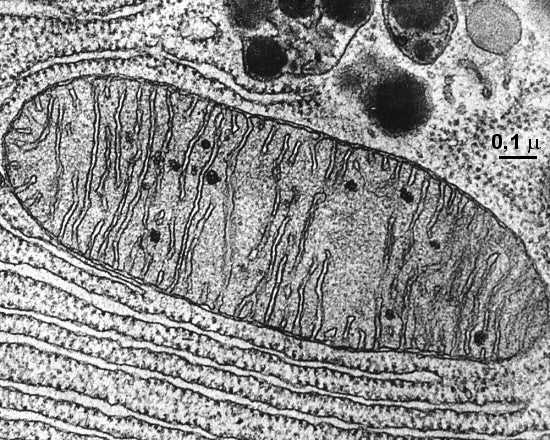

Mitochondrien und ihre Rolle im Anti-Aging

AbstractMitochondrien, oft als „Kraftwerke der Zelle“ bezeichnet, spielen eine zentrale Rolle bei der Zellgesundheit und dem Alterungsprozess. Ihre Funktion beeinflusst nicht nur die Energieproduktion, sondern auch Prozesse wie die Zellregeneration...